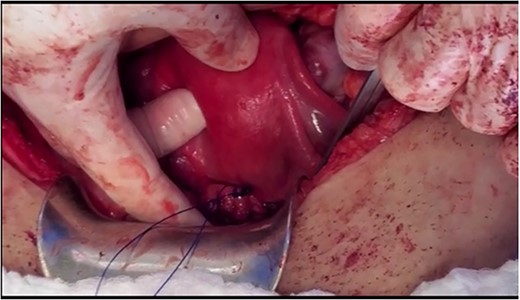

Under spinal anesthesia, supine position, the patient underwent laparotomy with a transverse skin incision and midline incision of the fascia. Exploration confirmed the pre-operative diagnosis. The retroperitoneal space was entered, and ureters were identified bilaterally. A window was opened (broad ligament) at the level of the uterine artery to ligate uterine arteries using ligasure, ureterolysis was done and both ureters were skeletonised down to the ureteric tunnel (as in radical hysterectomy). The uterosacral ligament and cardinal ligament were ligated using ligasure, at the level of the cervico-vagina junction. An anterior colpotomy was done after the dissection of the bladder and creation of the bladder flap, and the anterior colpotomy was extended laterally from each side by using ligasure with careful attention to keep the ureters away. The circumcision of the cervix was completed by using Heaney clamps at the vaginal angles. The uterus was mobilised along with the cervix and the myoma and completely separated from the vagina (Fig. 1). At this point, cautery was used to amputate the cervix with careful attention to maintain the integrity of the infundibulo-pelvic ligament (Fig. 1). The uterus was sutured to the vagina with the box technique, where the posterior aspect of the vagina and cervix was sutured, followed by the lateral and anterior wall. After that, one proline permanent suture was used as a cerclage, used to support the uterus for future pregnancy (Figs 2 and 3).

The cerclage placement after suturing the uterine isthmus to the vagina.